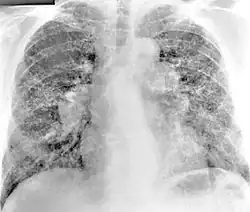

X-ray image of a 54-year-old man working in the aerospace manufacturing industry with berylliosis

Diagnosis of berylliosis is based on history of beryllium exposures, documented beryllium sensitivity, and granulomatous inflammation on lung biopsy. Given the invasive nature of a lung biopsy, diagnosis can also be based on clinical history consistent with berylliosis, abnormal chest x-ray or CT scan findings, and abnormalities in pulmonary function tests.[15]

Chest radiography findings of berylliosis are non-specific. Early in the disease radiography findings are usually normal. In later stages interstitial fibrosis, pleural irregularities, hilar lymphadenopathy and ground-glass opacities have been reported.[19][20] Findings on CT are also not specific to berylliosis. Findings that are common in CT scans of people with berylliosis include parenchymal nodules in early stages. One study found that ground-glass opacities were more commonly seen on CT scan in berylliosis than in sarcoidosis. In later stages hilar lymphadenopathy, interstitial pulmonary fibrosis and pleural thickening.[20]